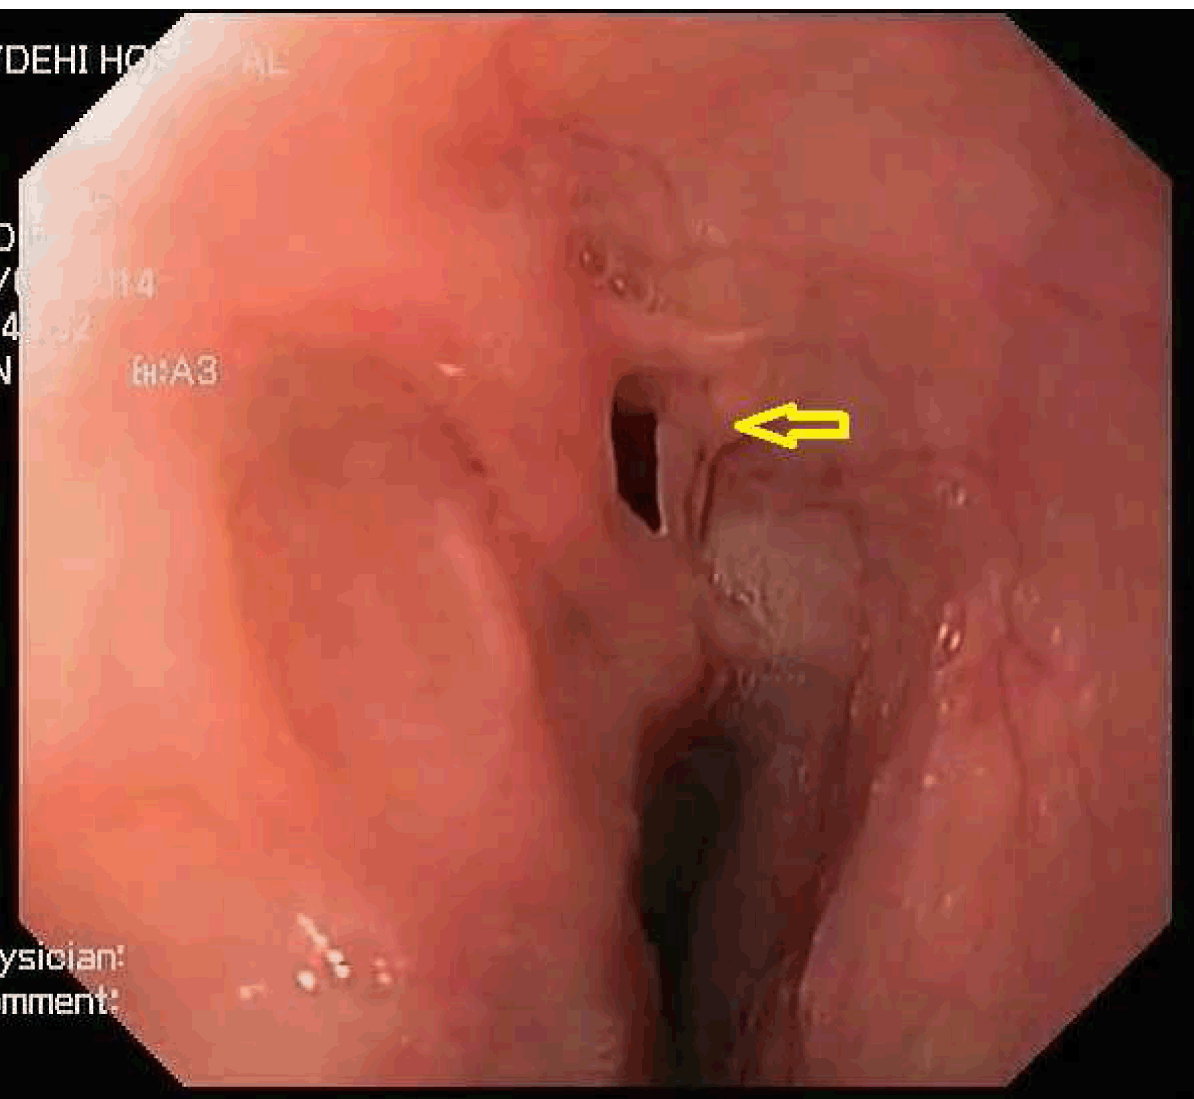

A 37-year-old male presented to our department with history of cough with expectoration immediately after taking food, especially liquids for last 13 years. He had two bouts of hemoptysis in the last 15 days which had made him seek medical attention. Clinically, chest on auscultation had crackles in right infra-scapular region. Chest X-ray revealed patchy opacities in the right lower zone paracardiac region. Computed tomography (CT) scan of thorax revealed consolidation in posterior segment of the right lower lobe with no evidence of lung sequestration or cyst. Upper gastrointestinal endoscopy showed a fistulous opening in the mid esophagus 32 cm from the incisor teeth. It did not show any evidence of malignancy, granulomatous disease or any other acquired basis for the fistula. Simultaneously, methylene blue was injected into the fistulous tract and bronchoscopy was done which was normal. Barium swallow showed fistulous communication between mid esophagus and right lower lobe bronchus at lower border of T7 with barium passing downward into the right lung (Figure 1).

Figure 1: Barium esophagogram showing esophagobronchial fistula between the middle third of the esophagus and the right lower bronchus with downward passage of barium (shown with arrow).